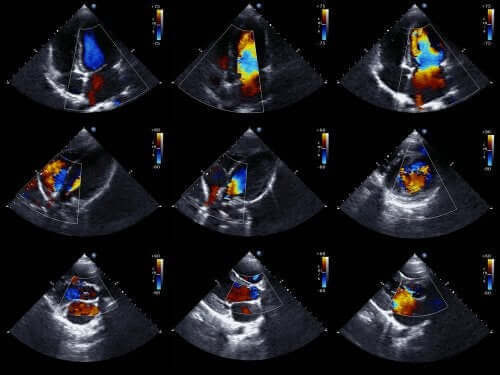

عادةً ما يستطيع الأطباء تشخيص هذا النوع من العيب الخلقي قبل ولادة الطفل. للقيام بذلك، يستخدمون مخطط صدى القلب للجنين. هذه تقنية تستخدم الموجات الصوتية لإعادة إنشاء صورة قلب متحركة.

وبفضل هذا، يمكننا أن نرى مظهر القلب ونفحص وظائفه عندما يكون الطفل لا يزال في الرحم. باستخدام هذه المعلومات، يمكن للأطباء وضع برنامج علاجي بعد الولادة مباشرة.